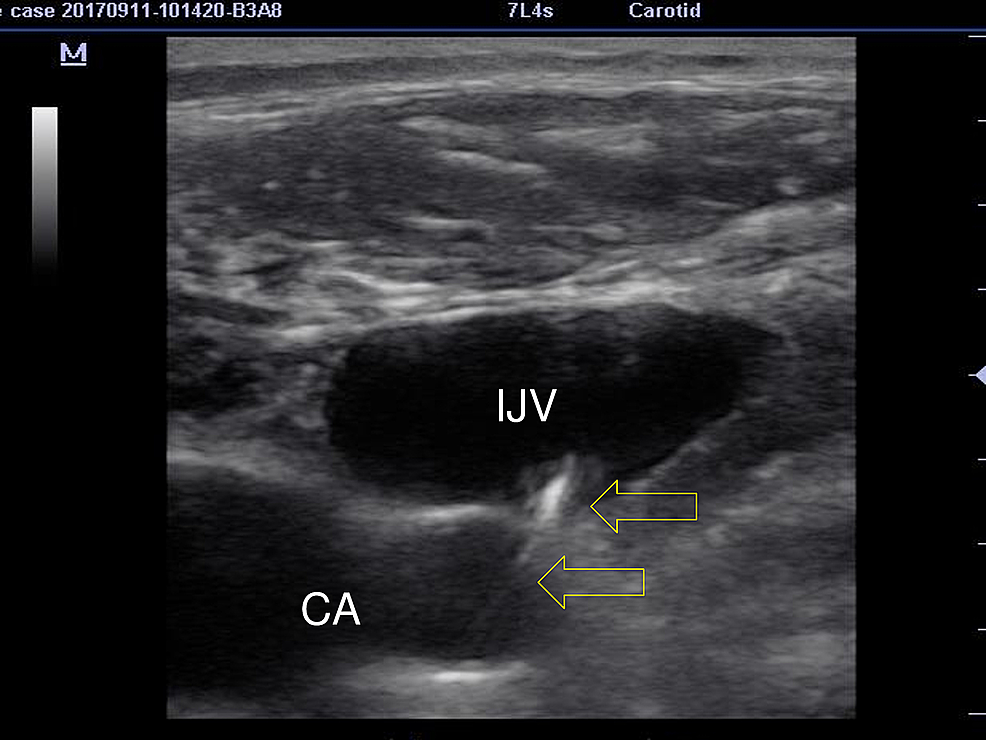

From www.semanticscholar.org

Figure 2 from Diagnosis of a missed central line guidewire using critical care ultrasound Guide Wire Central Line  The guidewire is used as a key to unlock the pack and to access the contents; Central venous catheter (cvc) is a cannula placed in a central vein (e.g. This activity reviews the indications, techniques, possible complications, and ways to reduce the risk of complications associated with central line. Secure the proximal end of the wire and continue to guide. Guide Wire Central Line.